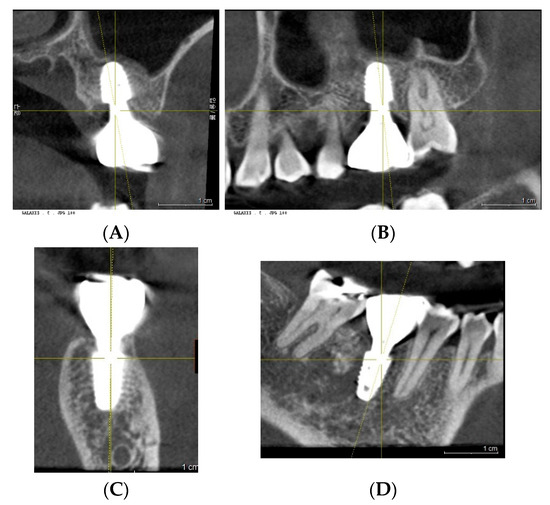

Background: Subcrestally placed implants (SPIs) present advantages for bone preservation and soft tissue support but pose challenges in maintaining peri-implant soft tissue health. This case explores the role of Crest to Restoration Distance (CRD) in the development and resolution of peri-implant mucositis. Case Presentation: A 57-year-old woman received two SPIs—one in the upper left and one in the lower right first molar region. Despite similar implant systems and prosthetic protocols, the upper left implant developed mucositis, characterized by bleeding on probing and discomfort, while the lower right implant remained stable. Three-dimensional analysis using cone-beam computed tomography (CBCT) revealed excessive CRD at the affected site. Results: After prosthodontic revision to reduce the CRD, clinical signs of mucositis resolved, with probing depths reduced to less than 1 mm and no bleeding on probing. The control site remained healthy throughout the observation period. Practical Implications: This case highlights CRD as a modifiable prosthetic factor influencing soft tissue stability. A three-zone model—comprising the sulcus, transitional zone (TZ), and subcrestal zone (SZ)—is introduced to provide a biologically grounded framework for understanding soft tissue adaptation around SPIs. Full article